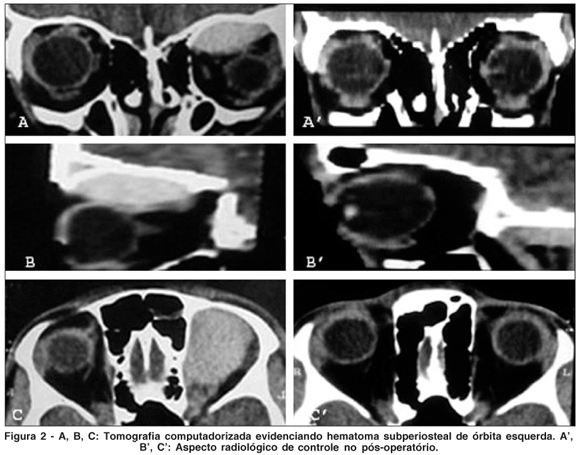

Submetido à tomografia computadorizada (TC) de crânio e órbita (Figura 2), foi evidenciada uma lesão hiperdensa de aspecto biconvexo no teto orbitário esquerdo. Realizou-se então orbitotomia que permitiu acesso à coleção sangüínea coagulada, sem pontos sangrantes ativos (Figura 1B). Procedeu-se à drenagem do hematoma subperiosteal orbital (HSPO). O paciente recuperou-se totalmente do quadro clínico descrito após a intervenção cirúrgica. Durante seguimento ambulatorial foi realizada TC de controle que se mostrou normal.

A TC de órbita com reconstruções sagitais e coronais permite o delineamento preciso do tamanho e extensão do HSPO. Possui as seguintes vantagens: a) define nitidamente uma massa não captante de contraste, hiperdensa, biconvexa com ampla base de implantação principalmente na porção superior do teto orbitário; b) permite a observação do HSPO em relação às outras estruturas vizinhas: tecidos moles, músculos conais, nervo óptico e globo ocular, e ainda mostra deslocamento inferior do conteúdo orbitário; c) demonstra estreitamento do nervo óptico(2,4).